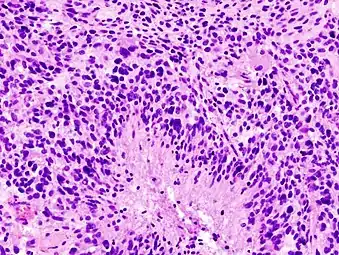

- Histopathology of glioblastoma, showing high grade astrocytoma features of marked nuclear pleomorphism, multiple mitoses (one at white arrow) and multinucleated cells (one at black arrow), with cells having a patternless arrangement in a pink fibrillary background on H&E stain.

- Lower magnification histopathology, showing necrosis surrounded by pseudopalisades of tumor cells, conferring a diagnosis of glioblastoma rather than anaplastic astrocytoma